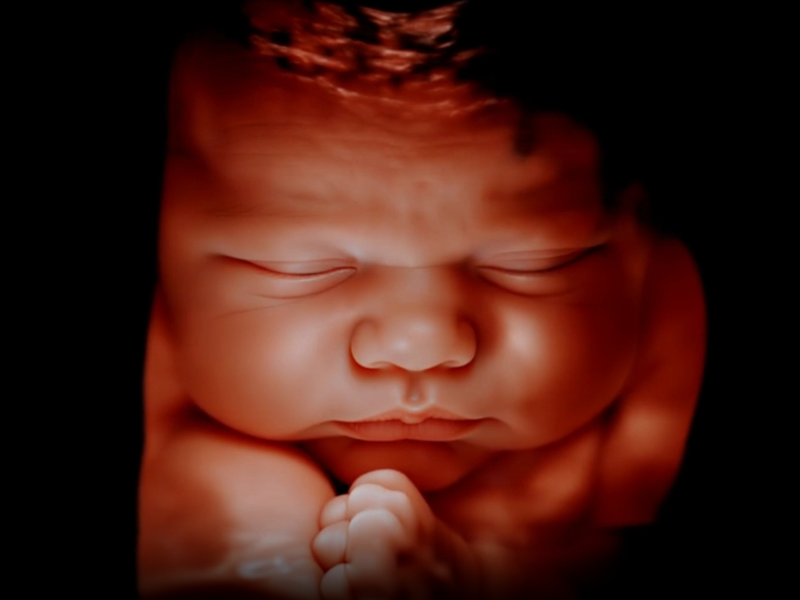

- A brief glimpse of your baby in 3D